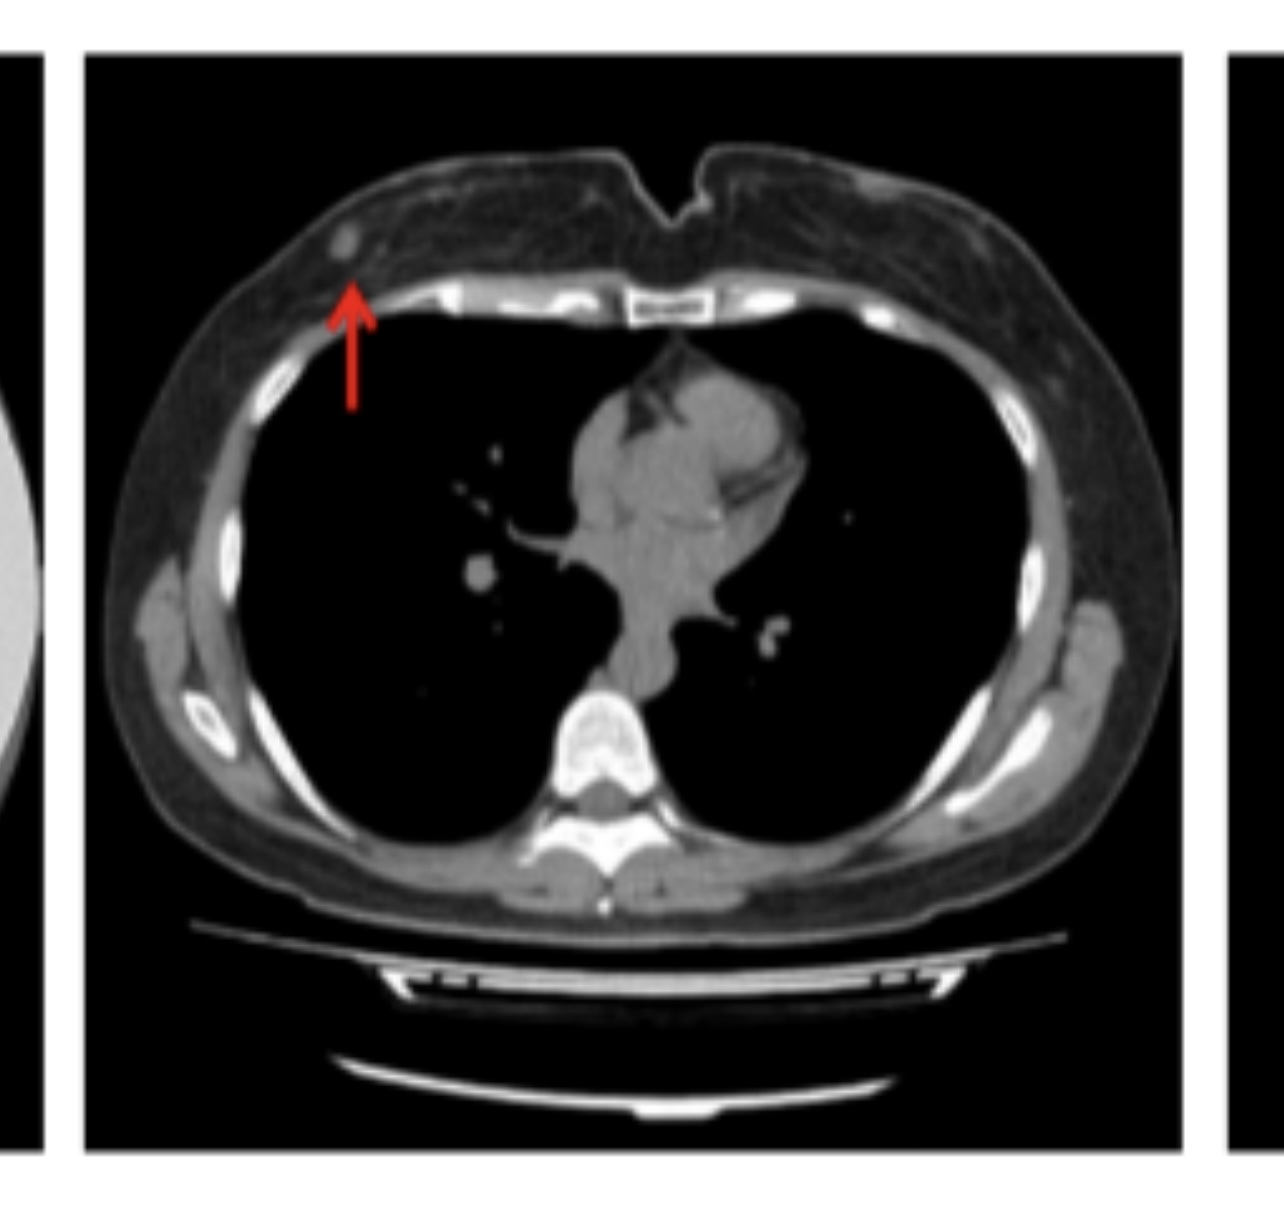

乳癌かも?しれんので

こないだ行ったチョコザップのCT結果で、乳癌かもしれんからちゃんと検査受けてーと通知が来たから、市のマンモグラフィーの券を請求した!えらい